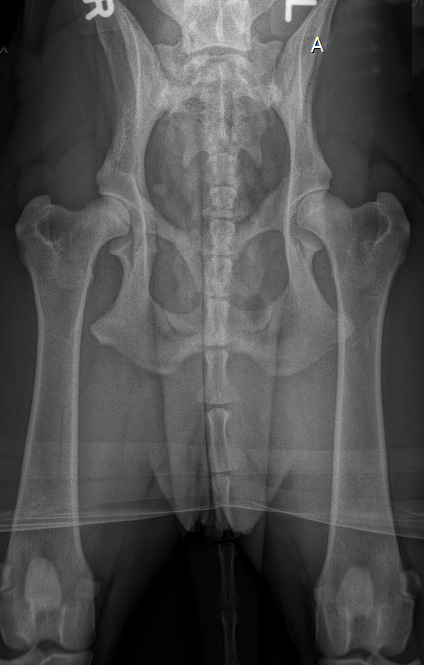

![]() HD-C/ HD-leicht/HD-2 (ab diesem Befund wird im ADRV e.V. kein Hund mehr zur Zucht zugelassen) |

C |

= Grad1 (leicht) |

HD-2 |

leicht |

Leichte Inkongruenz, divergierender Gelenkspalt, NORBERG-Winkel um 100 Grad |